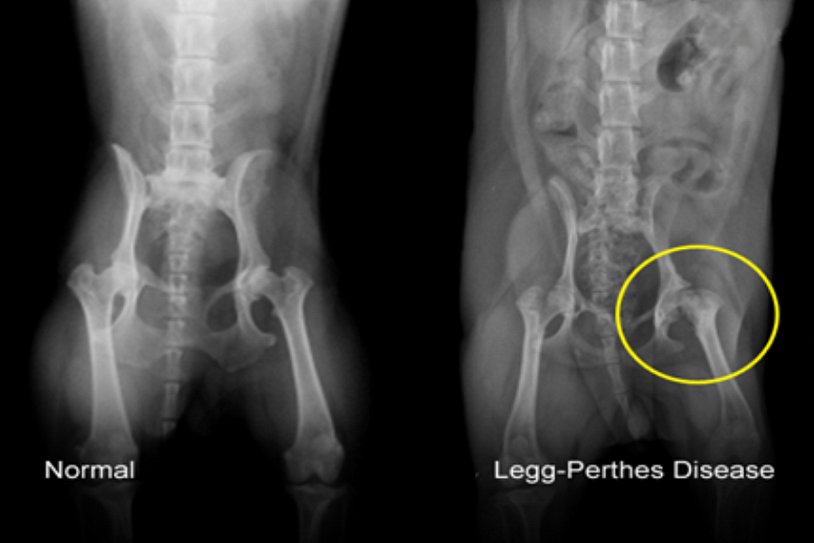

Диагностика ТБС рентгеном и асептический некроз: особенности лечения

Раздел: Снимки-откровения